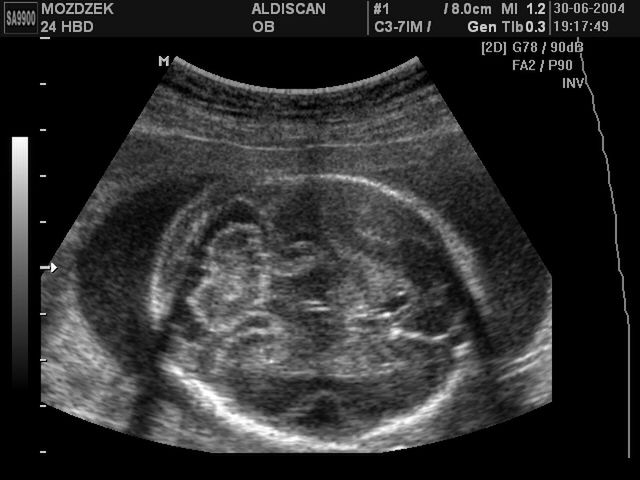

/ 10Zdjęcia płodu - 24 tydzień ciąży

Obraz

Płód w 24 tygodniu ciąży, na zdjęciu widoczny móżdżek dziecka